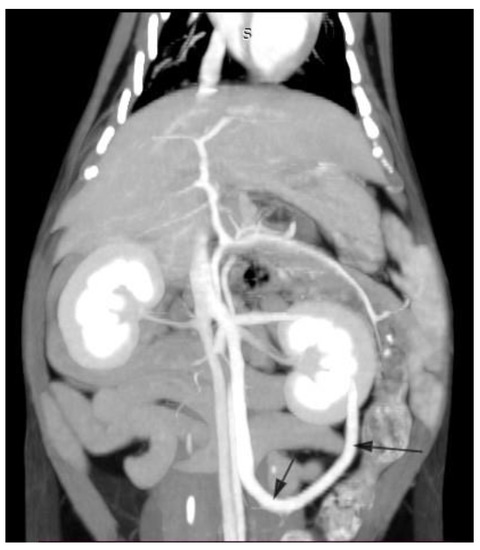

2.1. Case A (Human)

2.2. Case B (Human)